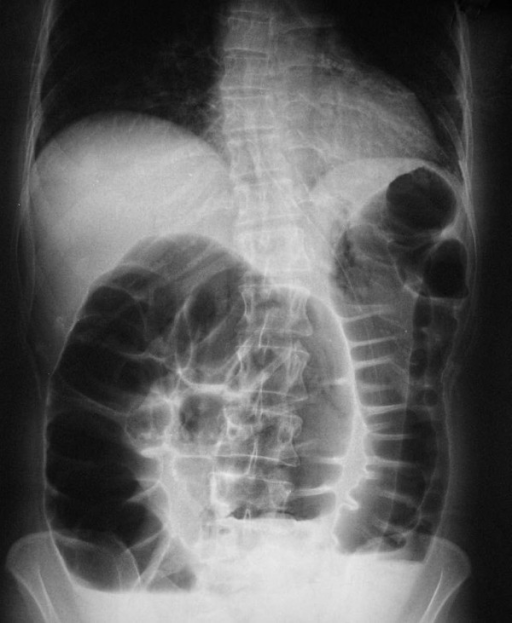

- Abdominal X-ray (best initial test) that would show dilated loops of small bowel

- CT scan of the abdomen and pelvis would show dilated loops of small bowel and any masses present